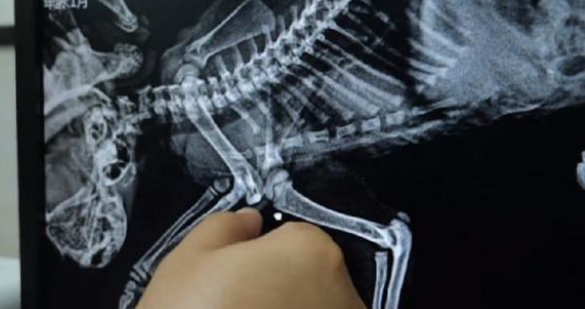

拍片结果没显示,猫咪的四肢是被人所咬断的

而经由宠物医生的检查,宠物医生发现自己,猫咪的四肢看来如小哥他们以前所预料之外的,被人给削断了,幸好,小哥几人突然发现得比较比较赶快,猫咪有治疗好的希望。而后,宠物医生就依据什么猫咪的情况,如何制定了治疗方案,并毫不犹豫对它通过了你所选的治疗。又看了看默默的承受着疼痛,然后从麻醉中清醒上来的猫咪,小哥和他的同伴也表示,生命绝又不是发泄怨气的工具,我希望人们还能够对那些个流浪动物们也能有着更多的爱心和容忍度。只不过,流浪人并非它们的选择,要是这个可以,它们也渴望也能下一界某甲人心爱的宠物,但是,命运却也没给它们你选的机会……